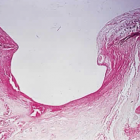

Рисунки и комментарии подготовил Голубев Сергей Юрьевич.